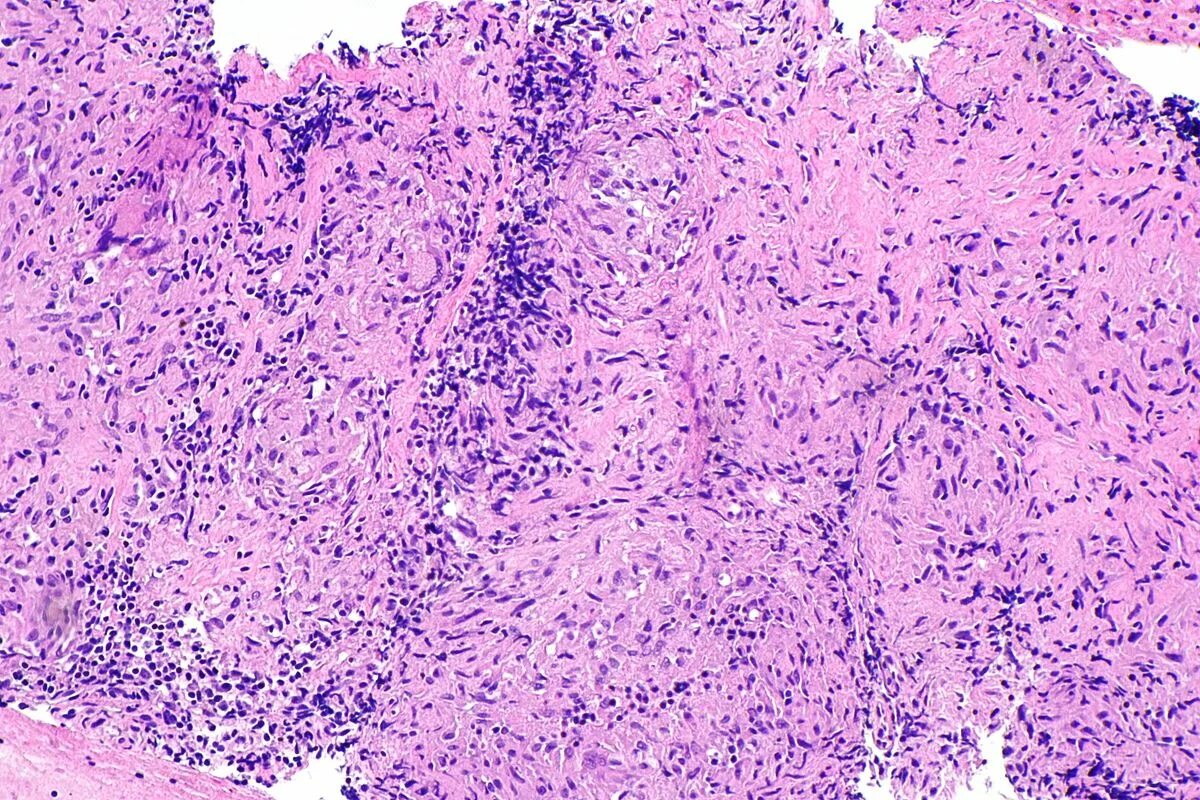

Гистологическая картина